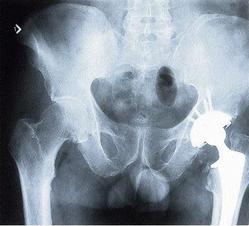

Numerous studies have been published on the topic. For example, one of the earlier studies published in Environmental Nutrition (December 1998) concluded, after studying 422 women in Sweden between 28 and 76 years old, that doubling the recommended intake of vitamin A could dramatically increase osteoporosis risk. The study found that hip fracture risk increased by 68 per cent for every one milligram increase in dietary retinol intake, confirming findings in animal studies.

Vitamin A intake and hip fractures, researchers say, are unusually high in Sweden, so it is perhaps not surprising that some of these studies focus on that population. Take this rather small study of only nine healthy individuals in Sweden, it pointed to the vitamin A in a serving of liver could possibly interfere with vitamin D's ability to promote calcium absorption. Researchers in Sweden also studied 250 women with a hip fracture against a control group of 875 participants.

They compared bone mineral density and retinol intake and found that taking more than 1,500 mcg of retinol per day was associated with reduced bone mineral density and an increased risk for hip fracture when compared to women taking less than 500 mcg retinol per day.

There was a large study, the Nurses' Health Study, which studied 72,337 post-menopausal women which also concluded that long-term intake of high amounts of vitamin A could promote hip fractures in post-menopausal women. In this study, there was an 18-year follow-up of participants and 603 hip fractures from low or moderate trauma were identified.

The researchers indicated that those women with the highest quintile intake of retinol (taking 2,000 mcg (6,667 IU) or more of vitamin A per day) had an 89 per cent higher risk for hip fracture when compared with the women in the lowest quintile (taking less than 500 mcg (1,667 IU) per day).